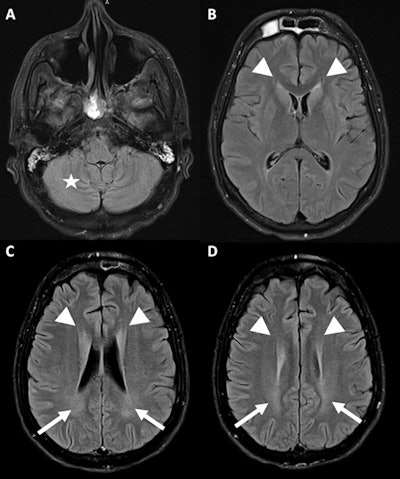

A 34-year-old man with a psychiatric history was found unconscious with heatstroke. FLAIR MRI sequence at the infratentorial level (A) with slight symmetrical cerebellar edematous changes collapsing the cerebellar leaflets (star), and supratentorial slices at the level of the lateral ventricles (B), corona radiata (C), and semioval centers (D), showing edematous changes of both caudate nuclei with collapse of both frontal horns (arrowhead) and slight increase in the signal of the biparietal periventricular white matter (arrows).There are several pathogenic mechanisms, according to the authors:

- Relative hypovolemia due to sweating and redistribution of circulating volume to the skin

- Release of proinflammatory cytokines with the possible development of systemic inflammatory response syndrome

- Direct injury to Purkinje cells from increased temperature

- Loss of the integrity of the gastrointestinal barrier with consequent bacterial/endotoxin translocation.

"These mechanisms are directly linked to imaging findings, either by cerebral hypoxia due to hypovolemia, presence of inflammatory cytokines/endotoxins that can lead to disseminated intravascular coagulation (DIC), or direct cerebellar neuronal damage," they stated.

Those findings can be categorized into two large groups of lesions:

- PRES-like lesions (vasogenic edema): cerebellar predilection, frequent supratentorial involvement of basal ganglia, and variable cortico-subcortical compromise

- Ischemic lesions (cytotoxic edema): predominantly supratentorial at subcortical level.

These two types of presentation are not mutually exclusive, and therefore patients with PRES-like findings on MRI may also have associated ischemic lesions, they added.